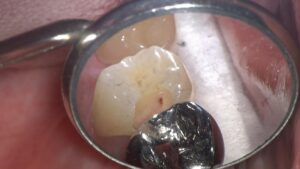

表層を除去し、虫歯を染色液で染め出します。

そして、健康な部分を触らないように虫歯の箇所のみ最低限除去していきます。

虫歯が全部取り切れた状態です。

歯の内部に点状に赤く見える箇所は、神経の一部が露出している状態です。

虫歯が神経の表層まで到達していました。